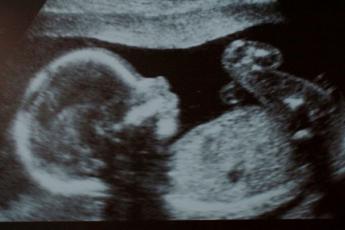

آغاز زایمان یک فرآیند پیچیده است که هنوز برخی از جوانب آن برای علم پزشکی مبهم است. یکی از سوالات اصلی این است که چه عاملی باعث شروع زایمان میشود و آیا فرمان تولد از مغز جنین صادر میشود؟ در این مقاله از رشت گشت به بررسی این موضوع خواهیم پرداخت.